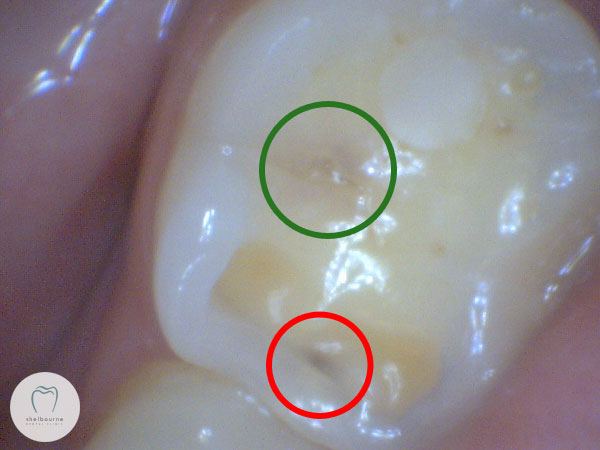

Picture taken of dark area in 2013. Looks like it might need a filling to me…

I’ve circled the two interesting areas on the tooth. The green circle shows a slightly darkened area in the middle of the biting surface. This looks slightly suspicious, but it’s debatable if it’s enough to justify touching it. The red circled area is much more obvious, and my first reaction was that this might need to be filled. On the X-ray I took, nothing much showed up however.

It’s slightly out of focus, but it still shows the same dark areas fairly clearly. And comparing this picture to the first one, it’s immediately obvious the dark areas haven’t increased in the last four years at all. So this damage has clearly stopped progressing. Can I still justify filling this? I don’t think so.